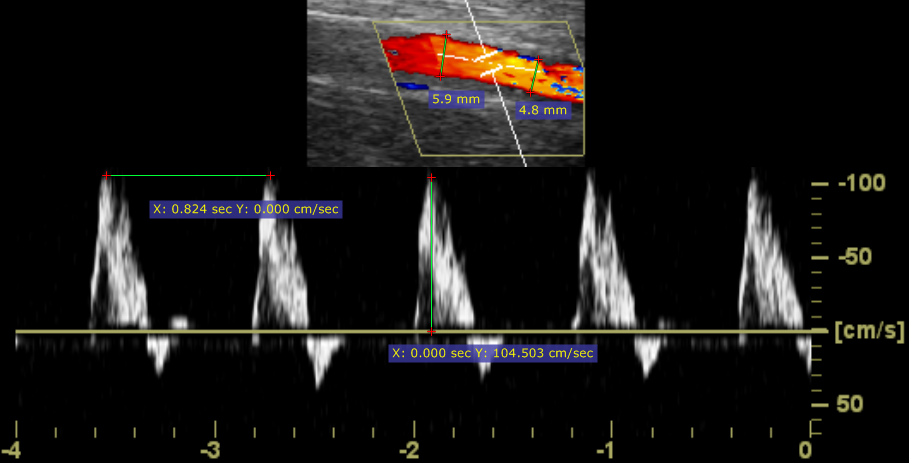

超声(US)图像中的测量

超声设备产生的 DICOM 图像通常包含经过校准的区域。根据区域类型,可以测量不同的参数。

下图为测量距离、速度和时间的示例截图。